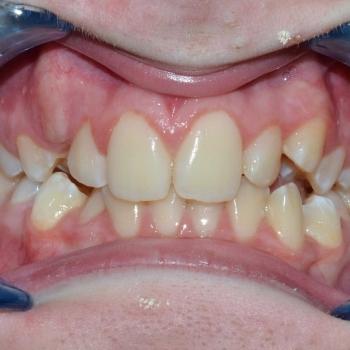

Kíra és édesanyja egy kollegám javaslatára kerestek fel a rögzített fogszabályzó számára legoptimálisabb időszakban, a tejfogak leváltása után, de még a 7-es fog előtörése előtt. Az első konzultáció alkalmával fény derült az alsó és felső fogív nagymértékű torlódására, a jobb felső szemfog kiszorult helyzetére és következményes felső középvonal eltolódására, illetve az enyhe mélyharapásra. A röntgenek kiértékelése után ez a kórkép kiegészült az alsó és felső metszőfogak hátradőlt pozíciójával, ami a kezelést nagyban megkönnyítette, mert lehetőséget adott mindkét fogív meghosszabbítására, így helynyerésre a torlódott fogazat számára.